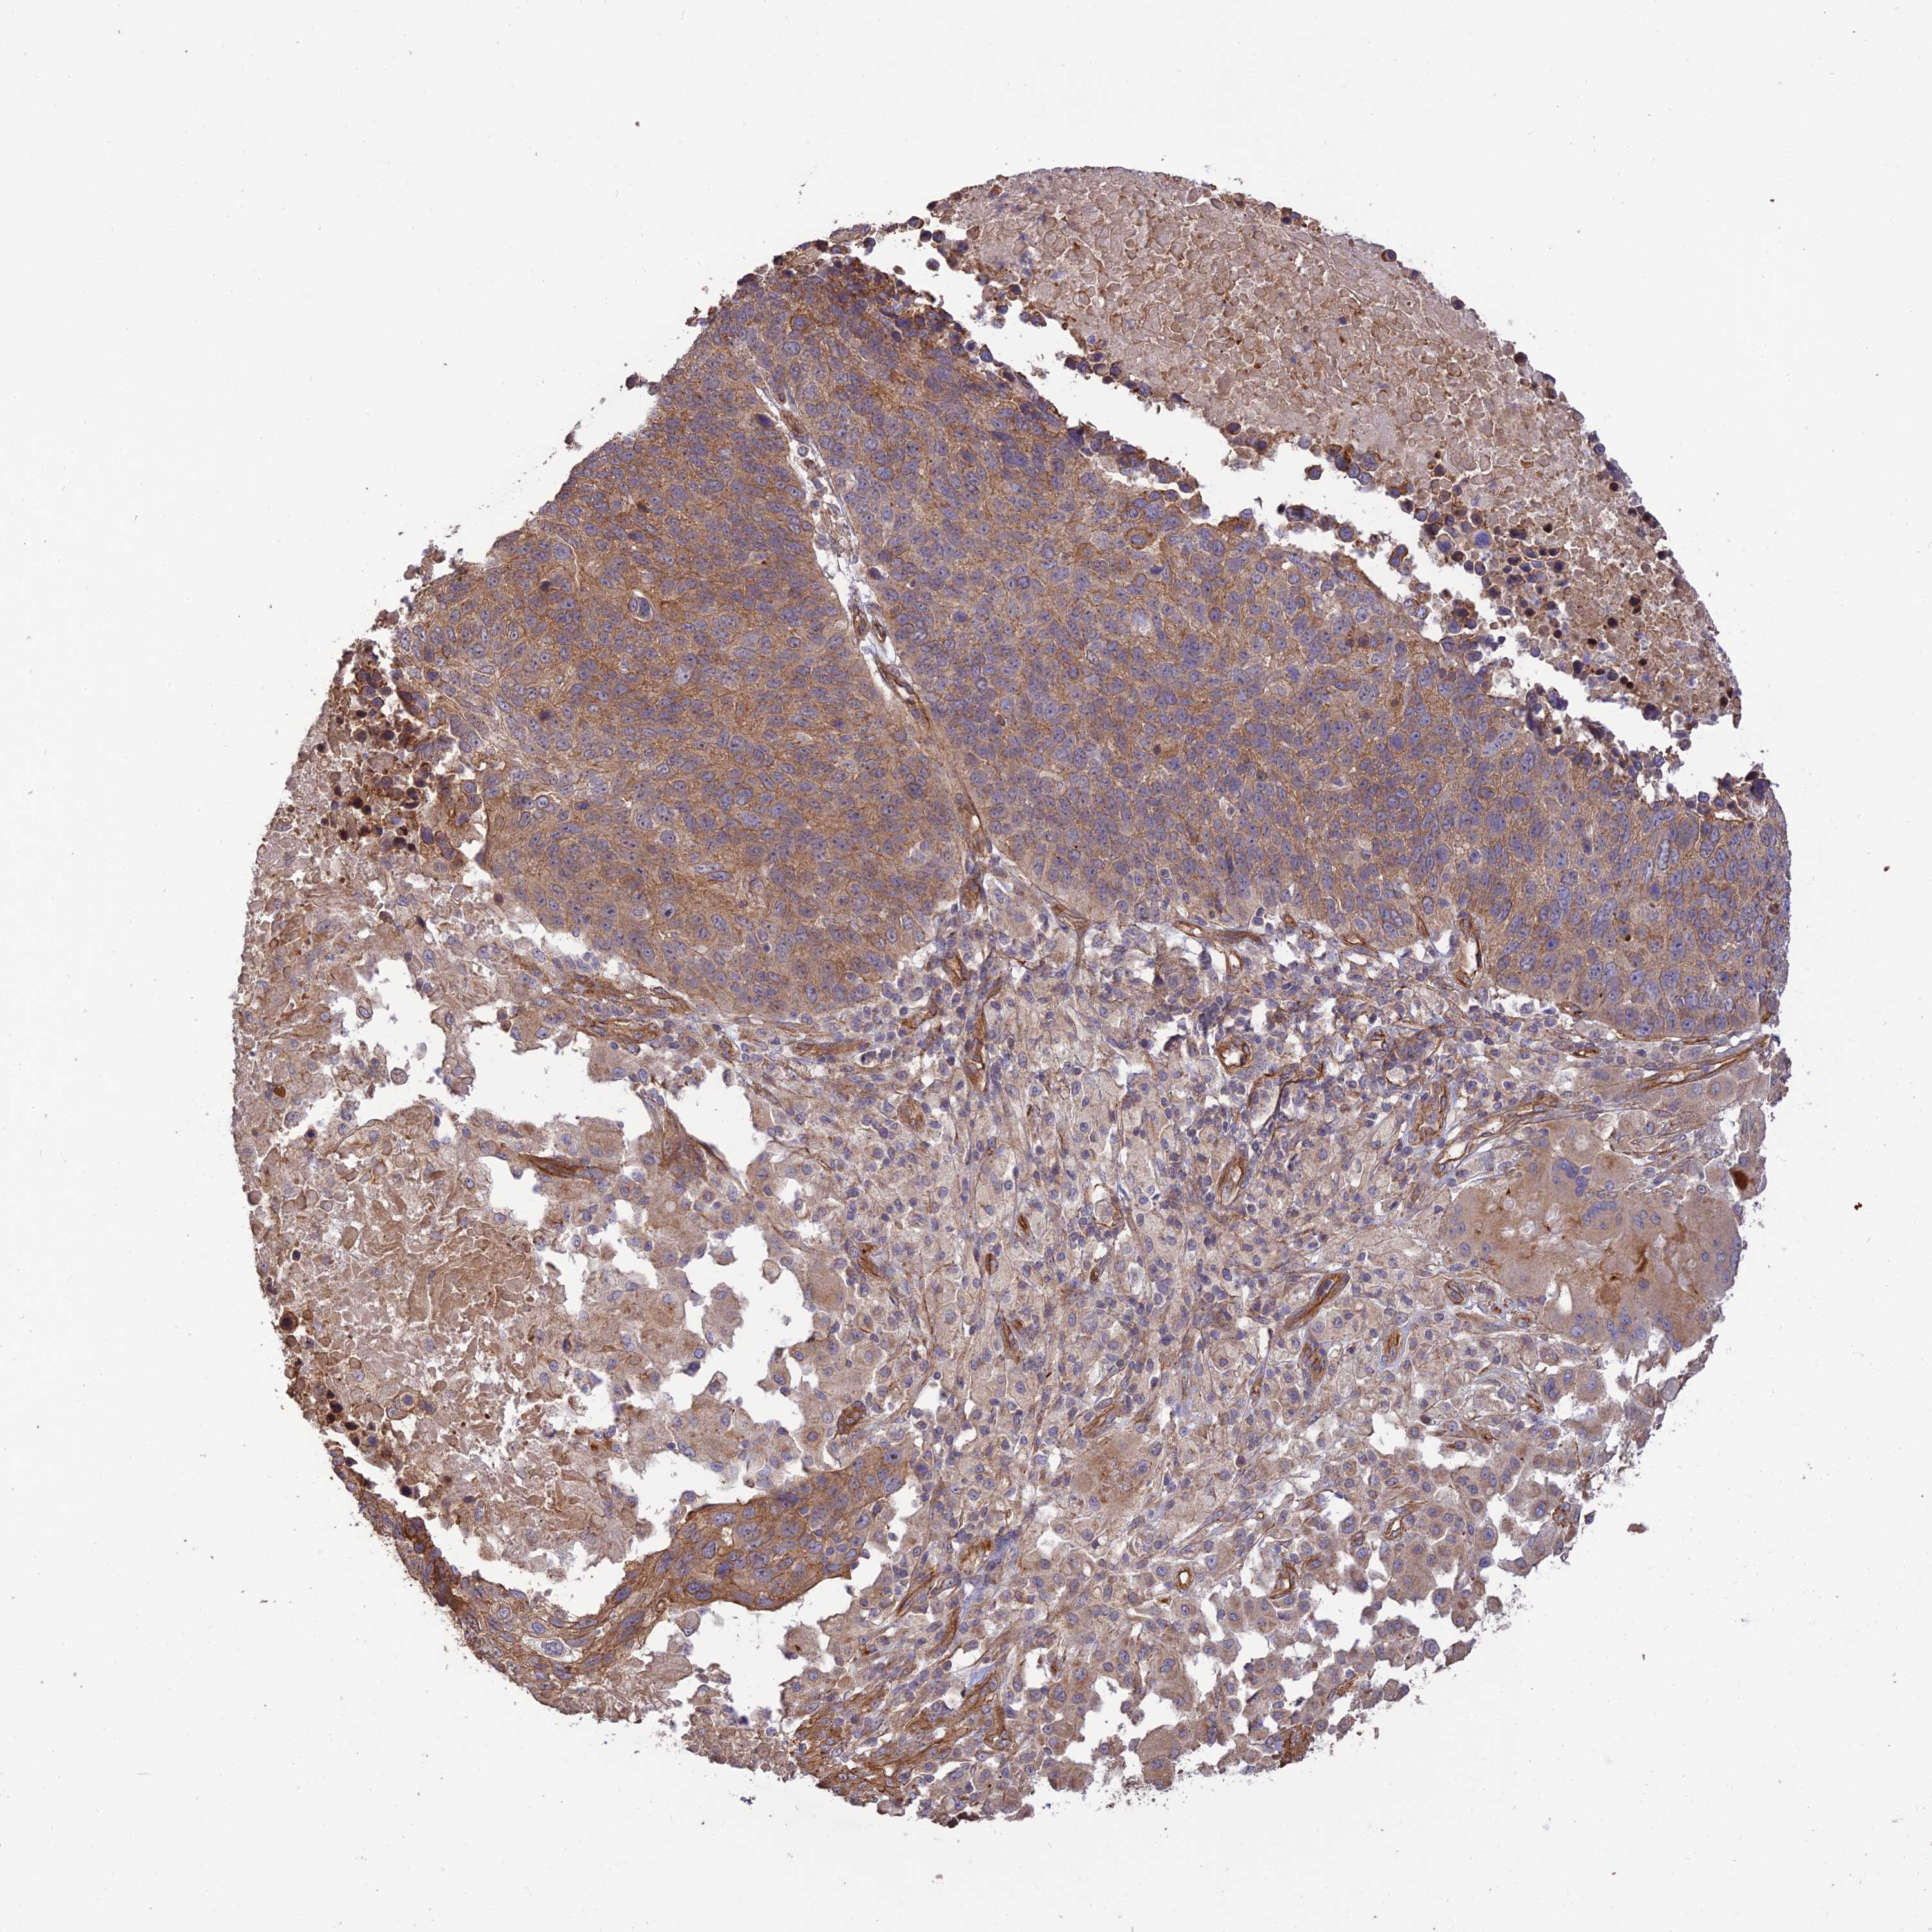

CANCER LUNG CANCER Show tissue menu

LUAD TCGA LUAD VALIDATION LUSC TCGA LUSC VALIDATION PROTEIN LUAD CPTAC PROTEIN LUSC CPTAC PROTEIN EXPRESSION